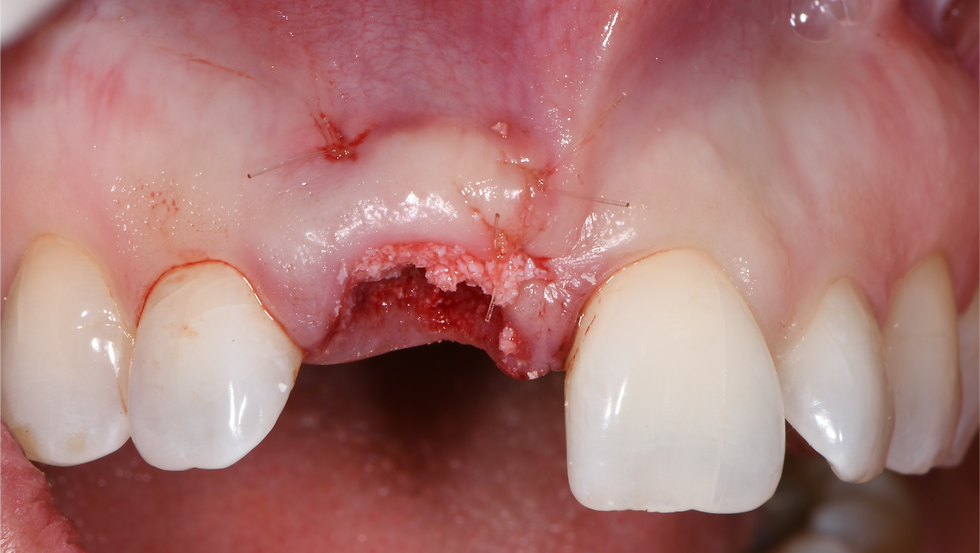

At the same time, a connective graft is taken from the maxillary tuberosity

The gap is filled with a particulate bone graft of porcine origin